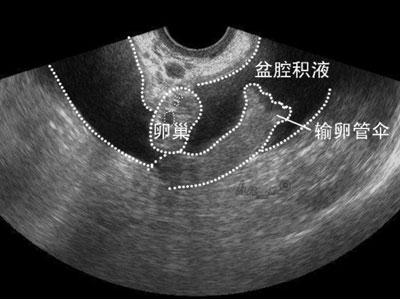

上面这张图片其实有点危言耸听了,盆腔积液也有非病理性的。

比如排卵的时候,卵泡液流入盆腔,那么B超看来就是盆腔积液,而这是非病理性的。

还有,如果近期做过宫腔镜、输卵管通液之类的手术,也难免会有积液,毕竟手术中液体流入盆腔集聚,B超看来也是盆腔积液。